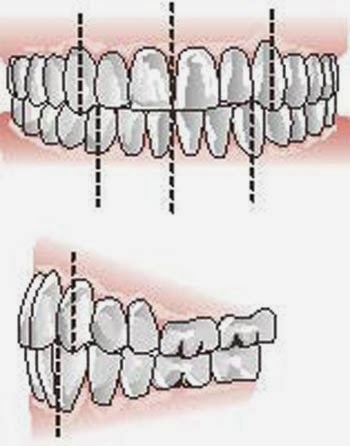

Maxillaire et mandibule – portant la denture supérieure et inférieure – sont en relation par

l’intermédiaire de l’articulé dentaire, système de référence unique et précieux lors des

réductions fracturaires (fig 1.4).